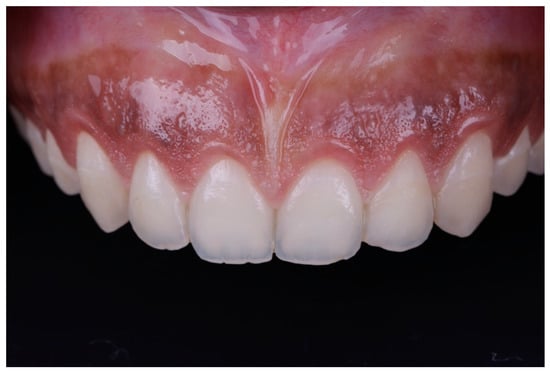

Figure 6.

Tooth length after gingival excision.